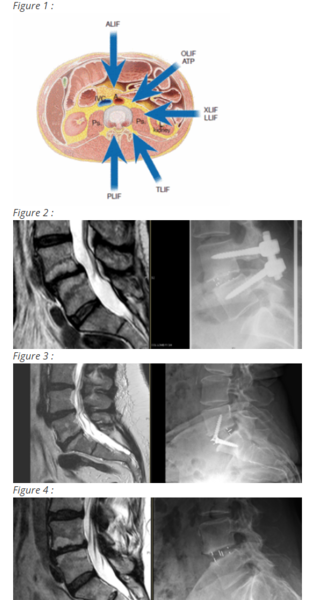

Différentes voies d’abord  et techniques ont été élaborées au fil des ans (figure 1). Les techniques qui restent le plus fréquemment utilisées à ce jour, sont les techniques dites postérieures. Elles associent le vissage pédiculaire à la mise en place de greffons intersomatiques par un abord postérieur (PLIF : laminectomie préservant les articulaires postérieures) ou par un abord postéro-latéral (TLIF : laminectomie avec arthrectomie) (figure 2). Ces voies d’abord autorisent une restauration partielle de la lordose (taille des cages limitée par la voie d’abord) mais surtout, permettent d’y associer un geste de décompression nerveuse. Lorsqu’elles sont réalisées de façon classique, elles occasionnent néanmoins, un affaiblissement des muscles paravertébraux. L’association fréquente des lombalgies dégénératives à des douleurs neuropathiques nécessitant une recalibration canalaire justifie toutefois le recours fréquent à ces techniques.

• La voie antérieure (ALIF) : incision sous ombilicale avec abord rétropéritonéal donnant essentiellement accès aux disques L4-L5 et L5-S1, le carrefour aortique limitant l’accès des autres niveaux (figure 3).

• La voie latérale (XLIF) : incision latérale avec abord retropéritonéal et à travers le muscle psoas ce qui expose à un risque de lésion du plexus lombaire. Cette technique permet un abord allant de L2 à L5.

• La voie oblique (OLIF) : d’apparition plus récente, elle est réalisée par une incision similaire au XLIF mais aborde le disque intervertébral par le bord antérieur du psoas en le respectant (figure 4). Elle permet d’accéder également de L2 à L5 mais limite donc fortement le risque de lésion du plexus lombaire. Elle est donc dorénavant préférée au XLIF.